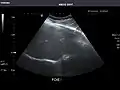

Left kidney -

Kidneys: Right and left kidneys measure 11.5 cm and 12 cm in length respectively. No hydronephrosis. Small left lower pole kidney cyst.